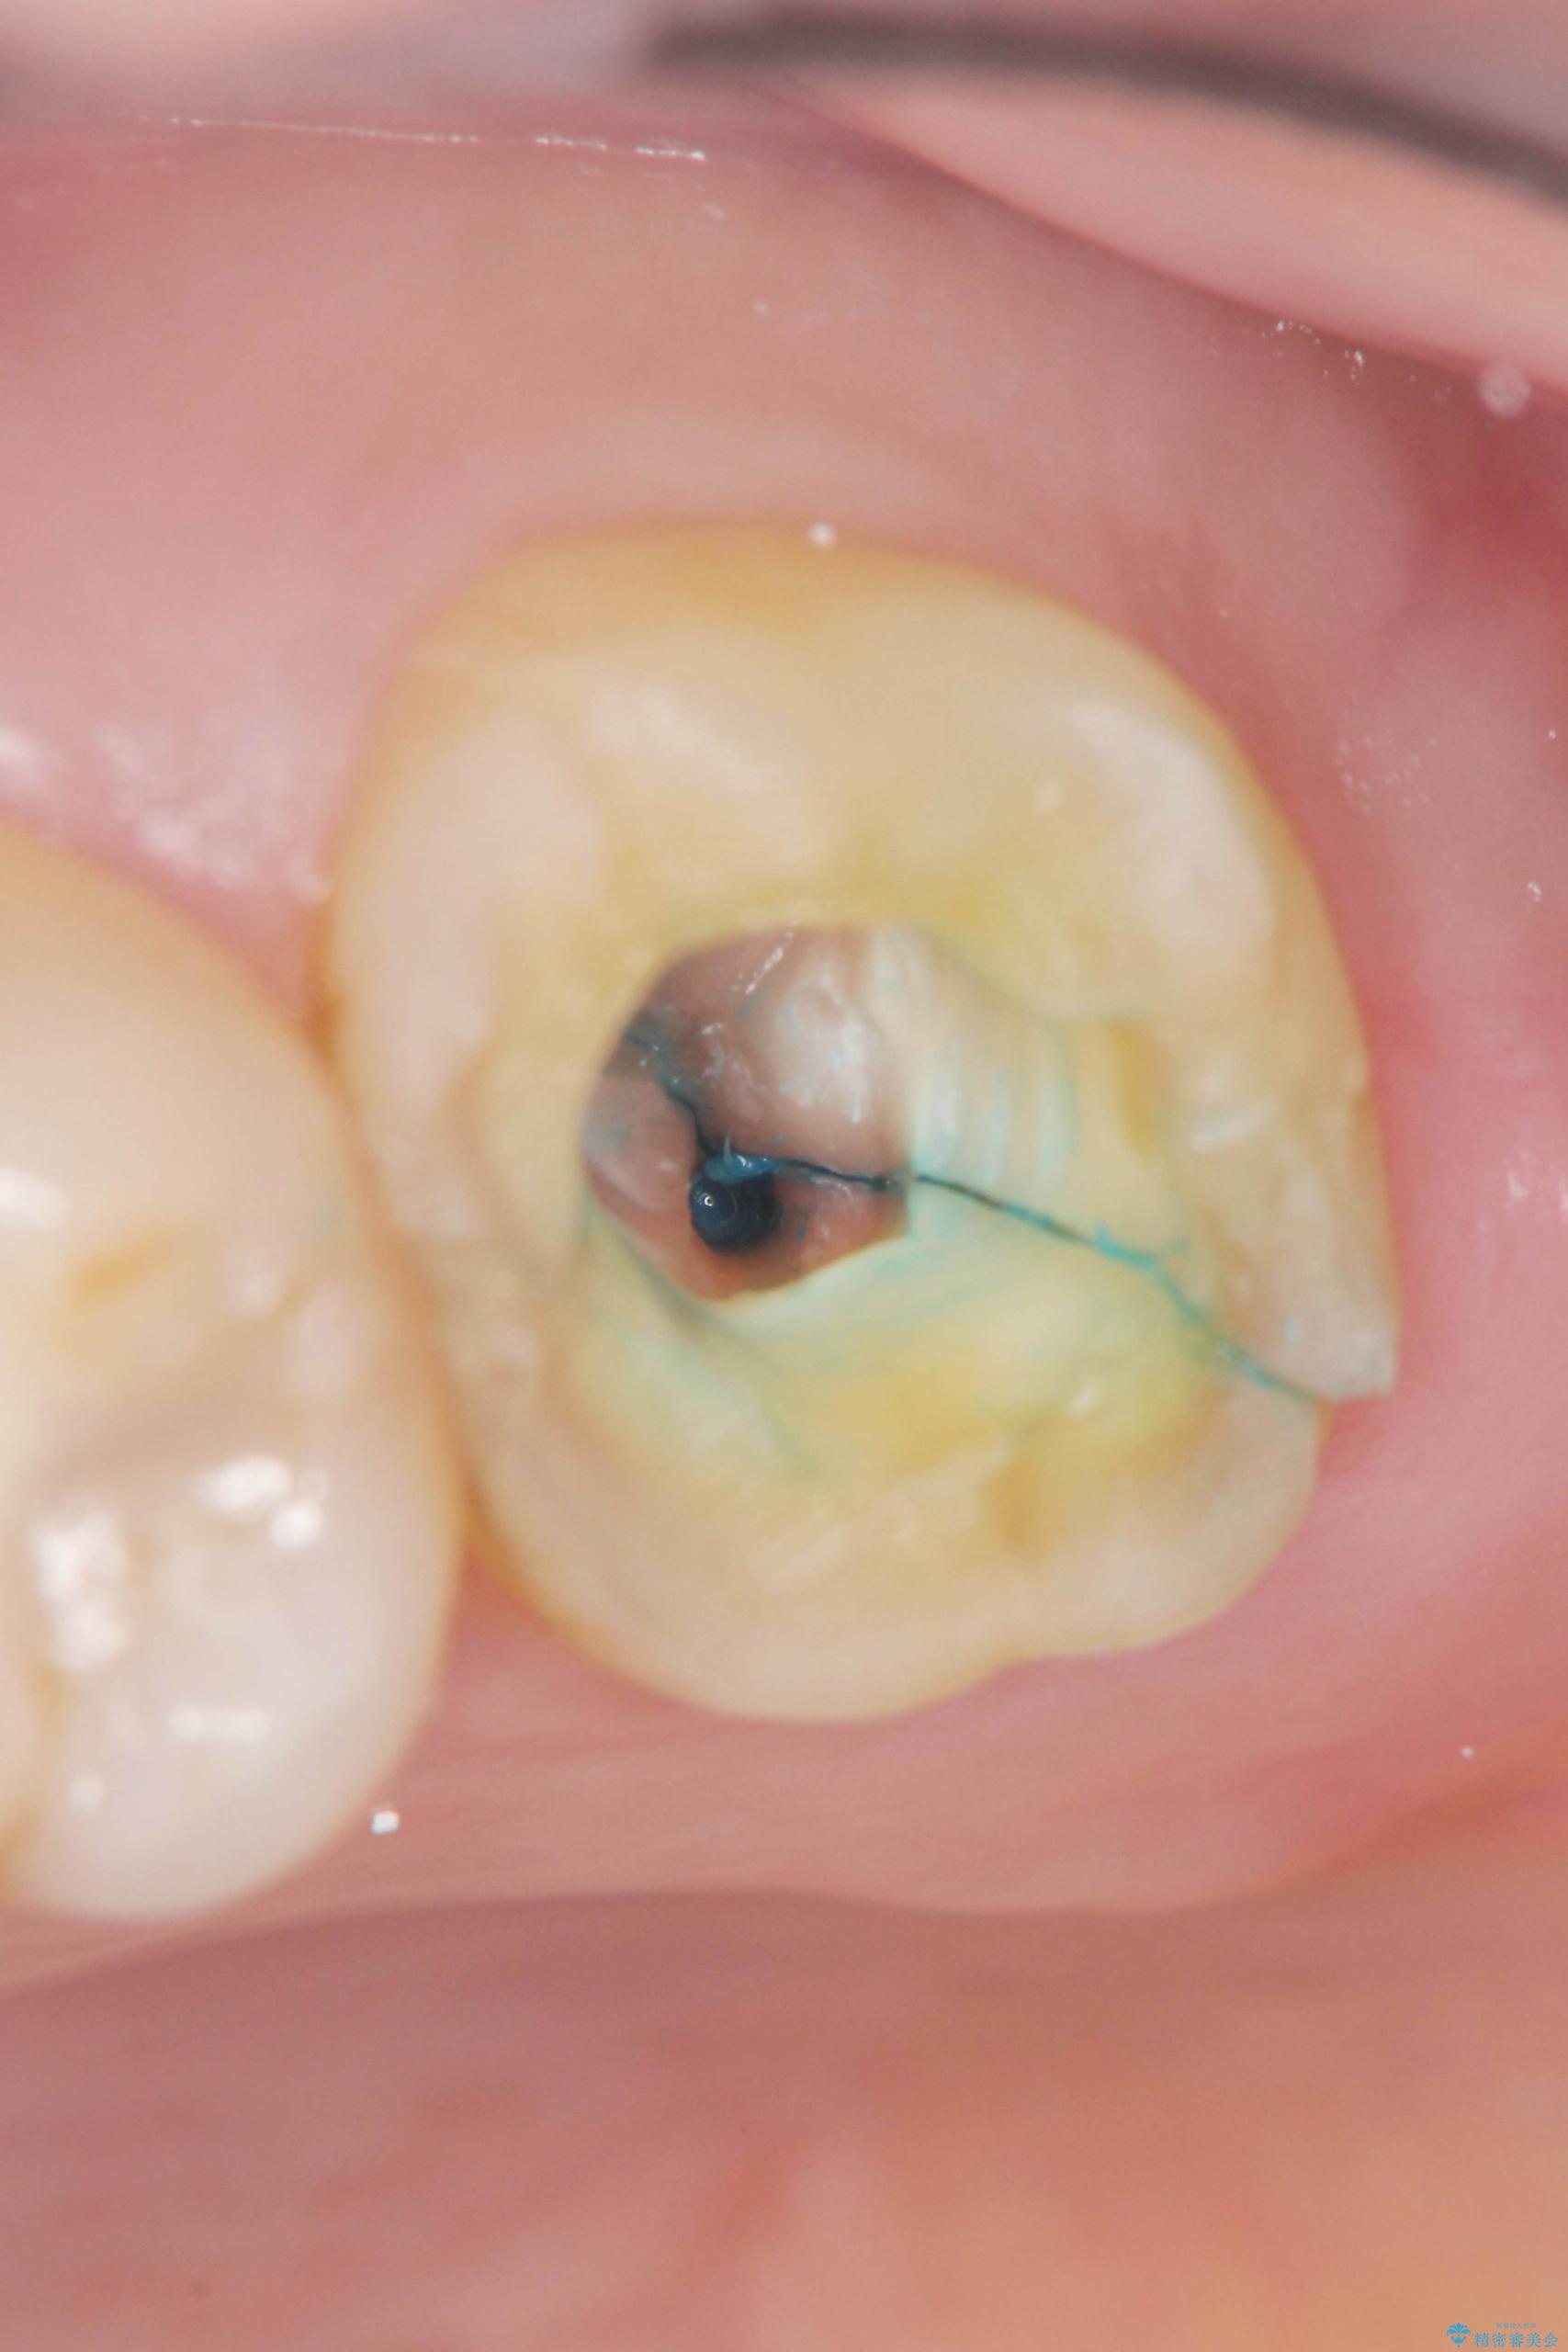

精査した結果、上顎奥歯は歯が割れてしまっており、根管治療ではなく抜歯の対象でした。

治療中

【噛むと歯が疼く】歯牙破折からのインプラント治療 治療中画像 【噛むと歯が疼く】歯牙破折からのインプラント治療 治療中画像 【噛むと歯が疼く】歯牙破折からのインプラント治療 治療中画像 【噛むと歯が疼く】歯牙破折からのインプラント治療 治療中画像